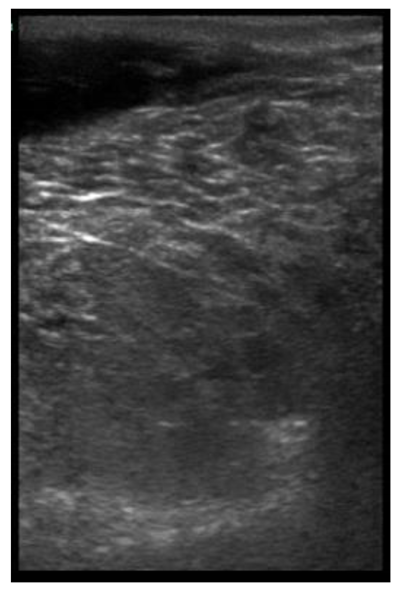

| 109 days of pregnancy (P109) Scanning depth 4.7 cm | ![]() | ![]() | MT generous: 36.8 mm MT conservative: 27.2 mm Gland cistern: 4.7 mm Parenchyma: 15.4 mm Fat Pad: 5.5 mm |